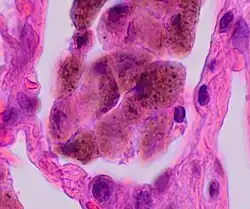

Comparison of pigmented pulmonary macrophages

| Disease | Macrophage name | Macrophage pigment appearance (HE stain) | Usual macrophage location | Associated medical history | Image | Image comment |

|---|---|---|---|---|---|---|

| Respiratory bronchiolitis | "Smoker’s macrophages" | Yellow to light brown and finely granular[4] | Airways (especially respiratory bronchioles) | Tobacco smoking |

|

Smoker's macrophage in center |